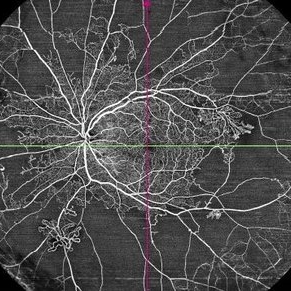

Proliferative Diabetic Retinopathy

This is widefield optic coherence tomography angiography (WF-OCTA) picture of LE of a diabetic patient. This patient had Proliferative Diabetic Retinopathy and depicts large areas of capillary non perfusion with neovascularization elsewhere.

Photographer: Dr. Kanwaljeet Harjot Madan, Thind Eye Hospital, Jalandhar City (Punjab) INDIA.

Imaging device: Widefield Optic Coherence Tomography Angiography (WF-OCTA).

Condition/keywords: OCTA, proliferative diabetic retinopathy (PDR), ultra-wide field imaging